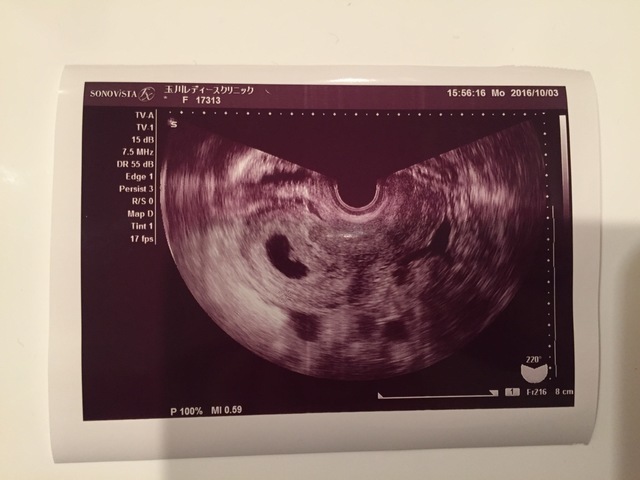

7週0日(7w0d・男の子)|わんちゃん さん(26歳)

エコー写真撮影時のエピソード:

妊娠が発覚した時、初めて撮ったエコー写真です。 当時ドキドキしながら行った婦人科で、ドラマで見たことしかなかったエコー写真を手にした時、とてもうれしい気持ちと、私が母になれるのかという不安と、こんなに小さい赤ちゃんがお腹に居るという感動は忘れられません。

当時つわりもありましたが、赤ちゃんの大きさは7ミリです、と先生からお話されてたった1センチも無い赤ちゃんが生きてる証拠なんだと、それ以降のつわりも愛おしく感じました。